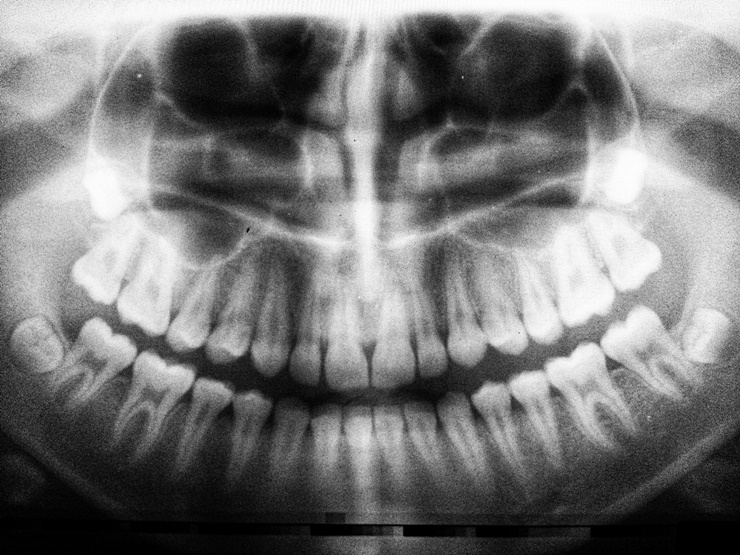

치아 추출 또는 발치의 경우에는 치아가 영구적인것이라고 하더라도 사람이 살아가면서 일반적인 거치는 과정이다. 주로, 이가 암염 도는 충치, 잇몸 질환, 외상으로 인한 손상, 사랑니 등으로 인해 발치를 시작하게 된다. 발치후 잇몸뼈가 제대로 자라지 않는 경우가 발생할 수 있다. 이 글을 통해, 발치후 잇몸뼈 회복 방법에 대해서 알아보도록 하자.

발치후 잇몸뼈 회복 방법에 대해서 알아봤다. 주로 사랑니 발치 후 잇몸뼈나 치조골에 대해서 관심이 많다. 치조골이 소실되게 되면 결국 임플란트를 할 수 밖에 없다. 부작용으로 발치 후 치열이 나타날 수 있으며, 뼈이식보다는 자신에게 맞는 상황에 따라서 대처하는 것이 가장 옳은 방법이라고 생각된다.